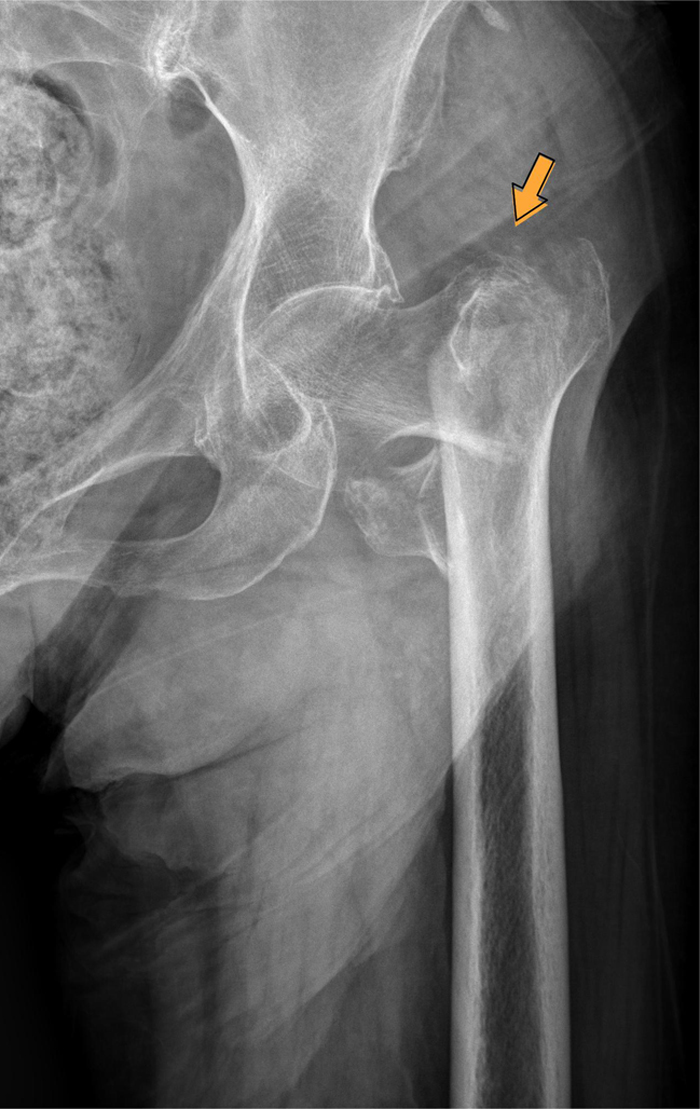

术前

近日,骨中间借助绿色通道又成功救治了一位98岁高龄髋部骨折患者。四月初,朱奶奶在家掉慎摔伤,当即感到左侧髋部苦楚悲伤难忍,无法起身行走,被家眷紧急送到潞河病院。急诊骨科大夫接诊后敏捷完美检查,明白诊断为左股骨转子间骨折,于是第一时光启动绿色通道收入骨中间创伤骨科病区。患者入院后,医疗部敏捷批示调剂,骨中间召集骨科、麻醉科、手术室、心内科、老年医学科科、内渗出科等多学科专家敏捷会诊,合营制订了详尽的术前检查与手术筹划。经由周全评估与检查,清除了手术禁忌后,朱奶奶于入院12小时内顺利进入手术室,由龙安华副主任医师、杨琦医师实施机械人帮助下左股骨转子间骨折微创髓内钉内固定术。凭借团队精深的技巧和丰富的经验,在骨科机械人精准帮助下手术用时仅40分钟,出血量少于50毫升,以最大年夜程度的微创方法顺利完成了手术。